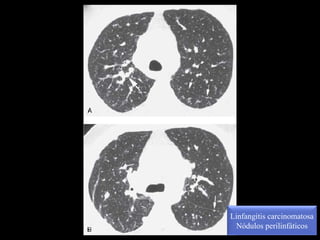

Linfangitis carcinomatosa

Nódulos perilinfáticos